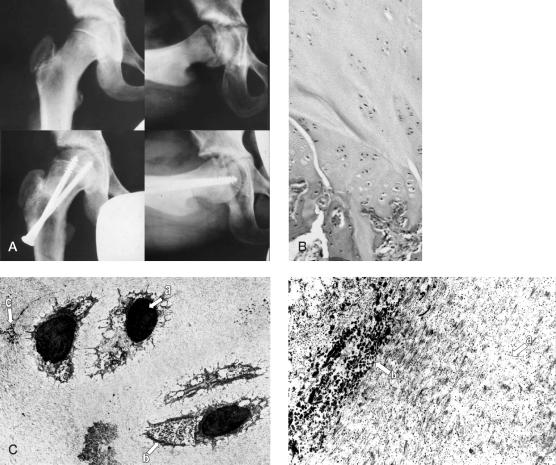

Several different theories have been proposed to explain the pathogenesis of slipped capital femoral epiphysis (SCFE). Using transmission electron microscopy (TEM), we carried out an ultrastructural study of core biopsy specimens of the physis at various stages of the disease.

Core biopsies were performed in 6 patients with different forms of SCFE during the first operation, and in 3 of them when removing the osteosynthesis material before physeal closure. The specimens were prepared for TEM examination.

In 6 specimens obtained at first surgery, a marked distortion of the physeal architecture was observed. In 2 of the 3 specimens obtained at removal of the osteosynthesis material, the physis showed a more normal organization.

The improvement of the pathological alterations observed in the 2 cases after surgical intervention leads us to consider the possibility that when the growth plate is stabilized directly by pinning or indirectly by creating more optimal loading conditions with an intertrochanteric osteotomy, the morpho-functional characteristics of the physis can be restored and its growth process may resume.